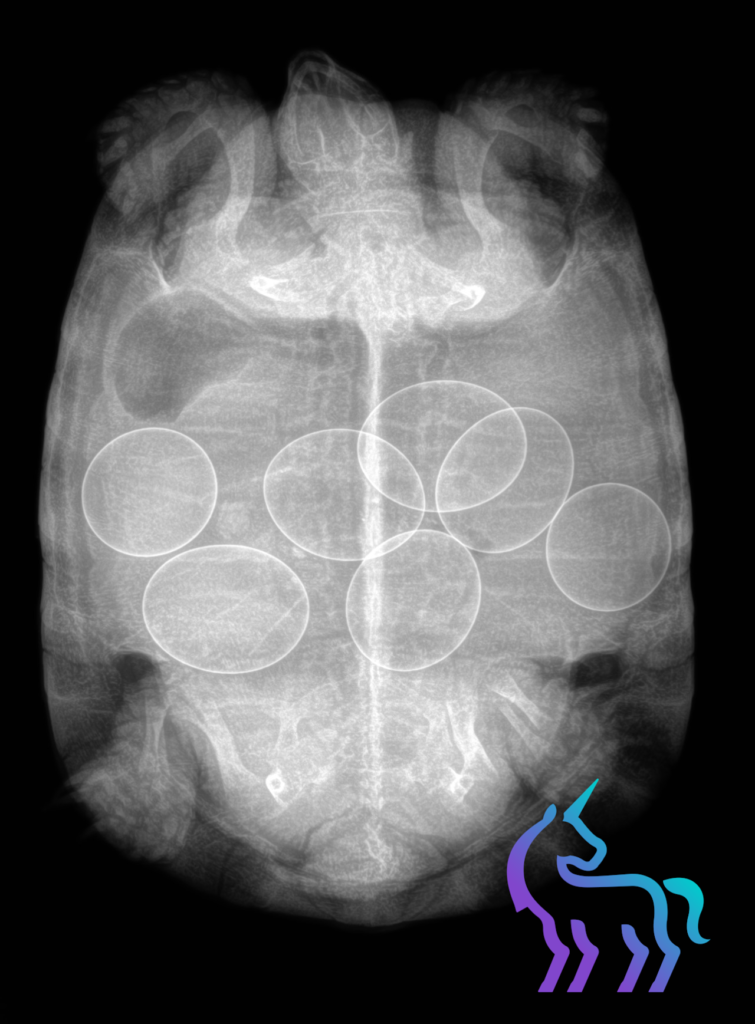

Radiographie tortue oeufs © Lingostière Clinique vétérinaire dans l’Art Radiographique